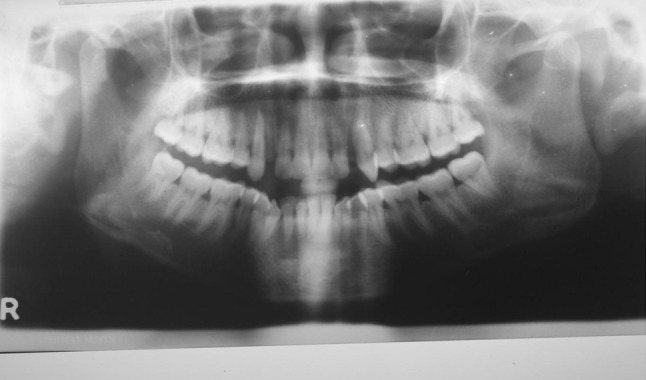

Fig. 15.

Pre-treatment IOPA of PLD Side

Fig. 16.

Pre-treatment IOPA of DAD Side